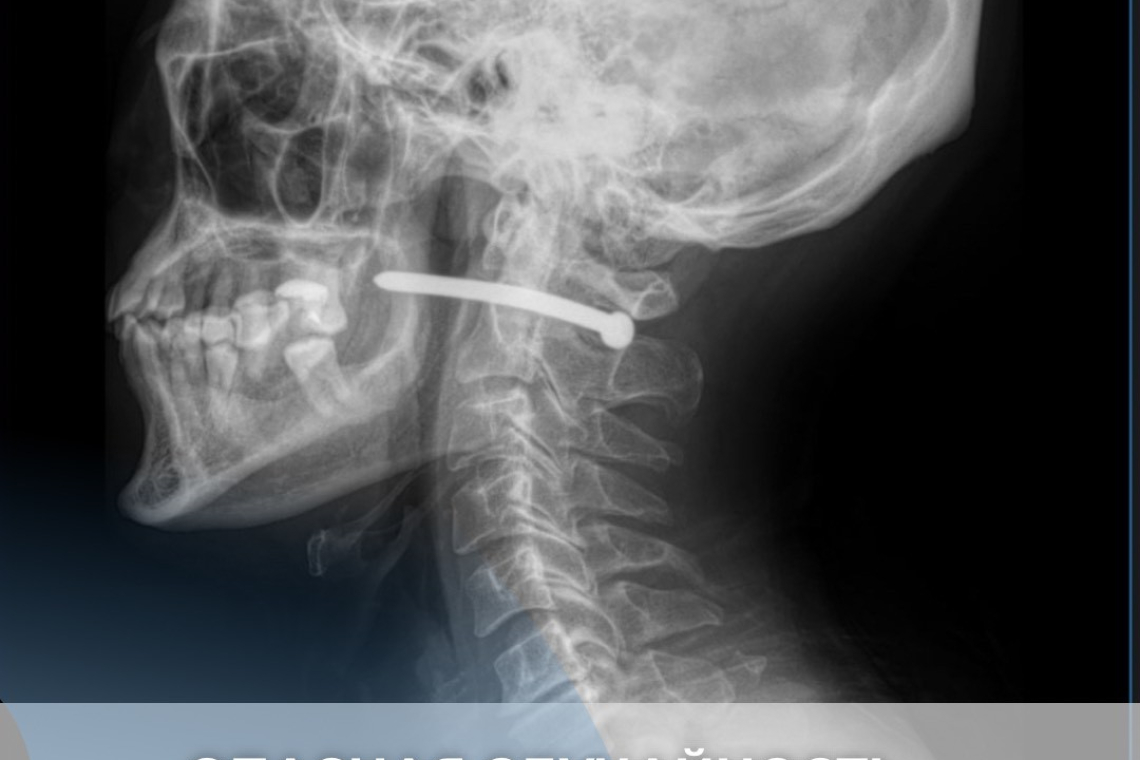

Во время ремонтных работ он по неосторожности получил травму гвоздём из пневматического пистолета.

После рентген-исследования выяснилось, что гвоздь прошёл рядом с шейным отделом позвоночника.

Мужчине чудом повезло — жизненно важные структуры не были задеты.